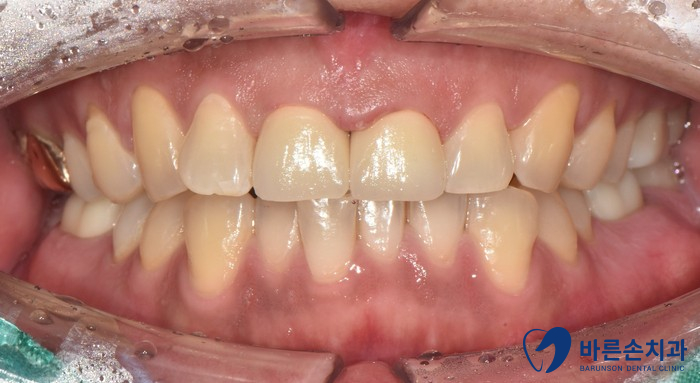

환자분의 경우 육안상으로 보아도 치아의 손상도가 커 보이는데요

치료 전 후를 비교해 볼까요?

치료전 치료후

자연스럽게 크라운이 완성되었네요.